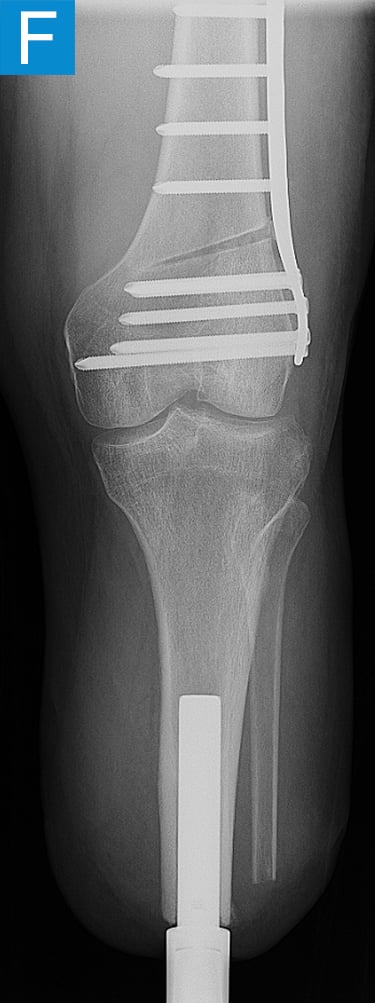

His first surgery was the transtibial amputation with simultaneous osseointegration. This entailed performing amputation of the tibia and fibula at the planned level, reaming and broaching the tibial canal to achieve a uniform canal for the diameter and length of the implant and inserting the osseointegration implant. This feels similar to how a cementless total hip femur implant mixed with an intramedullary nail might feel. Phantom nerve pain was prevented via regenerative peripheral nerve interface technique. Then the skin around the implant that passed through the skin portal was closed. His recovery followed the standard protocol of 4 weeks non-weightbearing followed by 4 weeks of progressive loading, with the prosthesis attached at 2 months (Figure 2). He quickly achieved a better gait than he had prior to amputation (Video 2) with essentially equal swing and stance per leg, but lateral knee pain persisted. Four months after osseointegration, a distal femur osteotomy was performed to neutralize his alignment.

Figure 2. Postoperative clinical photos and radiographs. (A) Front and (B) rear views show the patient standing with the osseointegrated tibia prosthesis. (C) Photo shows stable and healthy skin at portal site to be, although slightly dry due to the winter weather. The gold-colored metal is part of the permanent transcutaneous implant; the shiny silver-colored metal beneath the gold is part of the clinician-removable prosthesis connector, and the matte silver metal beneath features a screw at the front, by which the patient secures the prosthesis. (D) Standing coronal radiograph depicts residual genu valgum in the osseointegrated leg. (E) Lateral radiograph of the osseointegrated tibia. (F) Coronal radiograph of the left knee shows the distal femur osteotomy. (G) Final coronal radiograph after distal femur plate and screw removal shows well-aligned left leg with osseointegrated prosthesis.